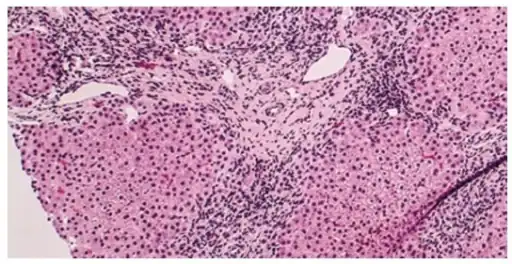

Histology of primary biliary cholangitis × 200 liver biopsy

On microscopic examination of liver biopsy specimens, PBC is characterized by chronic, non-suppurative inflammation, which surrounds and destroys interlobular and septal bile ducts. These histopathologic findings in primary biliary cholangitis include the following:[34]

- Inflammation of the bile ducts, characterized by intraepithelial lymphocytes, and

- Periductal epithelioid granulomata.

- Proliferation of bile ductules

- Fibrosis (scarring)

The Ludwig and Scheuer scoring systems have historically been used to stratify four (1–4) ‘stages’ of PBC, with stage 4 indicating the presence of cirrhosis. In the new system of Nakanuma, the stage of disease is based on fibrosis, bile duct loss and features of cholate-stasis, i.e. deposition of orcein-positive granules, whereas the grade of necroinflammatory activity is based on cholangitis and interface hepatitis. The accumulation of orcein-positive granules occurs evenly across the PBC liver, which means that staging using the Nakanuma system is more reliable regarding sampling variability.